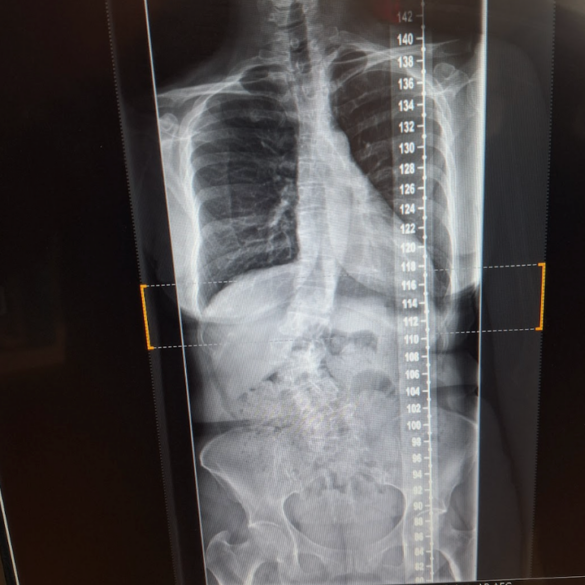

I stood before the screen gripping my lumbar, as the black-and-white X-rays stared back at me. I was 45 and...